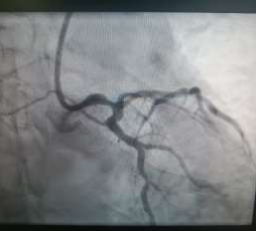

60 year old male known diabetic, hypertensive and dyslipidaemic presented with unstable angina, Coronary angiogram revealed Mid RCA pre crux lesion of 80-90% stenosis and PDA and PLV arising from Mid RCA (Fig 1). It was an angulated bend post bifurcation and hence Fielder FC wire support was taken to easily manipulate the vascular bifurcation (Fig 2) and successful PTCA+ stent to Mid RCA was done with 3x24mm Yukon choice flex stent (Fig 3& 4). TIMI III flow was achieved and post procedure period was uneventful.

FIG 1: Early bifurcating dominant RCA, Pre crux 90% stenotic lesion, with acute angled bifurcation